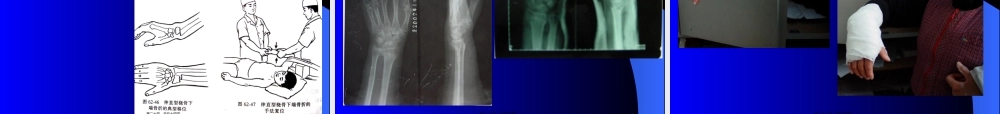

上肢骨折苏州大学附属第二医院骨科第一页,共五十四页。锁骨骨折肩锁关节脱位肱骨外科颈骨折肱骨干骨折肱骨髁上骨折前臂双骨折桡骨远端骨折第二页,共五十四页。锁骨骨折好发中1/3处第三页,共五十四页。第四页,共五十四页。第五页,共五十四页。肩锁关节脱位第六页,共五十四页。第七页,共五十四页。肱骨外科颈骨折年龄位置分类治疗第八页,共五十四页。第九页,共五十四页。肱骨干骨折容易损伤桡神经桡神经损伤的表现第十页,共五十四页。第十一页,共五十四页。第十二页,共五十四页。肱骨髁上骨折年龄容易损伤NV解剖分类治疗并发症第十三页,共五十四页。第十四页,共五十四页。第十五页,共五十四页。前臂双骨折第十六页,共五十四页。第十七页,共五十四页。桡骨远端骨折桡骨远端3cm掌倾角,前倾角分类:Colles,Smith,BartonColles骨折的畸形治疗第十八页,共五十四页。第十九页,共五十四页。第二十页,共五十四页。第二十一页,共五十四页。第二十二页,共五十四页。肩关节脱位第二十三页,共五十四页。第二十四页,共五十四页。第二十五页,共五十四页。肘关节脱位第二十六页,共五十四页。桡骨小头半脱位第二十七页,共五十四页。下肢骨折苏州大学附属第二医院骨科第二十八页,共五十四页。股骨颈骨折股骨转子骨折股骨干骨折髌骨骨折膝关节韧带损伤半月板损伤小腿骨折踝关节损伤跟骨损伤第二十九页,共五十四页。•股骨颈骨折第三十页,共五十四页。第三十一页,共五十四页。第三十二页,共五十四页。第三十三页,共五十四页。第三十四页,共五十四页。第三十五页,共五十四页。第三十六页,共五十四页。第三十七页,共五十四页。股骨转子骨折第三十八页,共五十四页。第三十九页,共五十四页。髌骨骨折第四十页,共五十四页。第四十一页,共五十四页。第四十二页,共五十四页。股骨干骨折第四十三页,共五十四页。第四十四页,共五十四页。膝关节第四十五页,共五十四页。第四十六页,共五十四页。第四十七页,共五十四页。第四十八页,共五十四页。胫腓骨骨折第四十九页,共五十四页。第五十页,共五十四页。第五十一页,共五十四页。第五十二页,共五十四页。第五十三页,共五十四页。内容总结上肢骨折。胫腓骨骨折第五十四页,共五十四页。